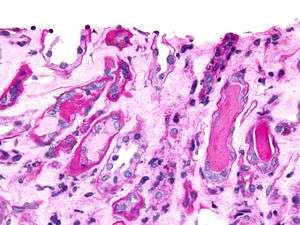

-

_HE_stain.jpg)

Bone marrow aspirate showing the histologic correlate of multiple myeloma under the microscope. H&E stain.

-

Plasmacytoma. H&E stain.

-

Micrograph showing myeloma cast nephropathy in a kidney biopsy. Hyaline casts are PAS positive (dark pink/red - right of image). Myelomatous casts are PAS negative (pale pink - left of image). PAS stain.

-

Atypical plasma cell infiltrate with both Russell (cytoplasmic) and Dutcher (nuclear) bodies (H&E, 50x).

Cellular morphology

The Plasma cells seen in multiple myeloma have several possible morphologies. Typical of plasma cells, they will usually have an eccentric nuclei. Because they are actively producing antibodies, the Golgi apparatus will typically produce a light-colored area adjacent to the nucleus, called a perinuclear halo. The cells may otherwise have the appearance of a normal plasma cell with a single nucleus and a single nucleoli with vesicular nuclear chromatin. Other common morphologies that are seen include:

- Bizarre cells, which are multi nucleated.

- Mott cells, containing multiple clustered cytoplasmic droplets or other inclusions (sometimes confused with auer rods, commonly seen in myeloid blasts)

- Flame cells, having a fiery red cytoplasm.[23] [24]